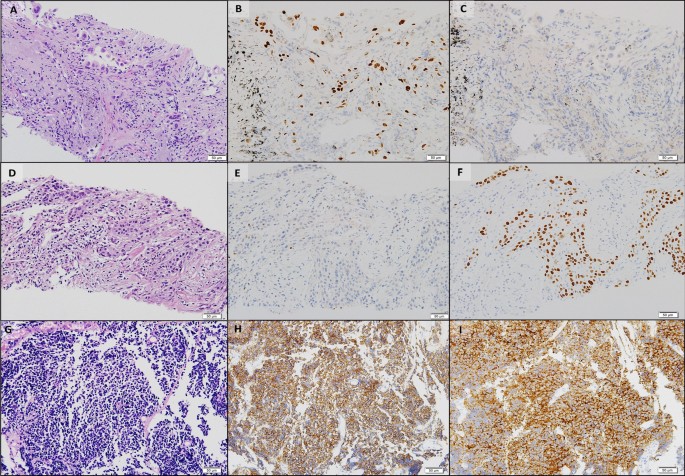

Histopathologic comparisons of the triple lung cancers. a-c The first tumor of adenocarcinoma at the right upper lobe. a Pleomorphic neoplastic cells with an acinar pattern (hematoxylin and eosin stain, ×200). b Immunoreactivity for TTF-1(×200). c Negative for P40(×200). d-f The second tumor of squamous cell carcinoma at the right lower lobe. d Polygonal cells with a solid pattern and no keratinization (hematoxylin and eosin stain, ×200). e No immunoreactivity for TTF-1(×200). f Strong staining of P40 at tumor cells(×200). g-i The third tumor of small cell carcinoma at the left lower lobe. g Small cells with scant cytoplasm and lack of nucleoli with a high mitotic activity (hematoxylin and eosin stain, ×200). h Positive neuroendocrine markers of CD56(×200). i Positive neuroendocrine marker of synaptophysin(×200). Equipment used to obtain images: Olympus BX53 microscope/Olympus objective lens WHN10X/22 UIS2, Olympus DP72 cameras and acquisition software: Olympus CellSens Standard 1.6 software. TTF-1, thyroid transcription factor-1